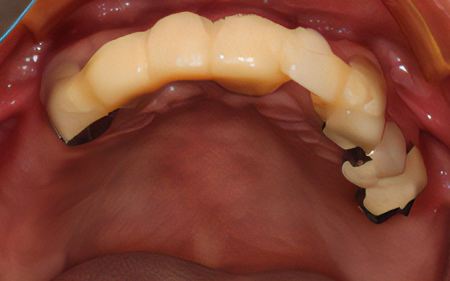

2024.08.1750代女性「歯科恐怖症で治療ができなかった。歯がボロボロで噛めない」インプラントとメタルボンドを入れ、物が噛めてご飯が食べられるようになった症例